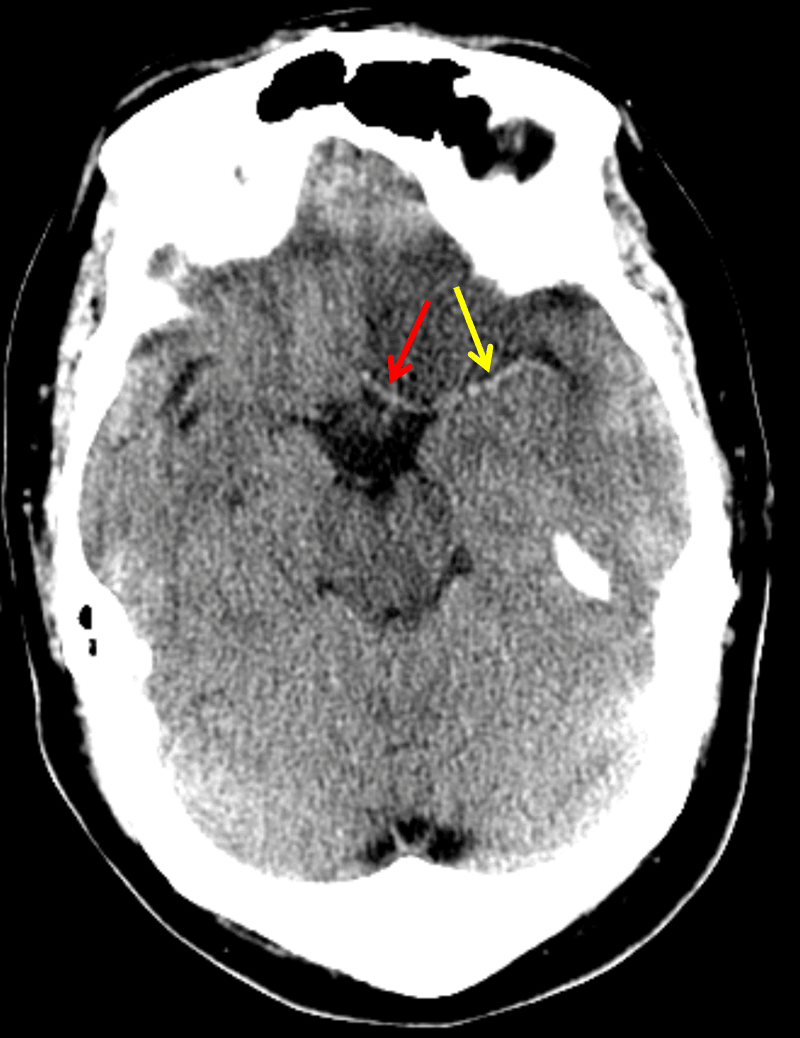

- Confluent low attenuation with loss of gray-white differentiation in the left cerebral hemisphere involving the ACA and MCA territories

- Asymmetrically hyperattenuating left MCA and ACA

- Left hemispheric sulcal effacement with slight left to right midline shift and slight effacement of the left lateral ventricle

Acute left ACA and MCA territory infarct

Diffuse, confluent low attenuation with loss of gray-white differentiation in the left cerebral hemisphere involving the ACA and MCA territories concerning for acute/early subacute infarct. Asymmetrically hyperattenuating appearance of the left MCA and ACA is concerning for thrombosis. Recommend head CTA and brain MRI for further evaluation.

No evidence of hemorrhagic transformation.

Associated cytotoxic edema with resultant left hemispheric sulcal effacement, 3 mm left to right midline shift, and mild narrowing of the left lateral ventricle. The basal cisterns are patent without evidence of herniation.

Asymmetrically hyperattenuating appearance of the proximal left ACA (red arrow) and MCA (yellow arrow) concerning for thrombosis